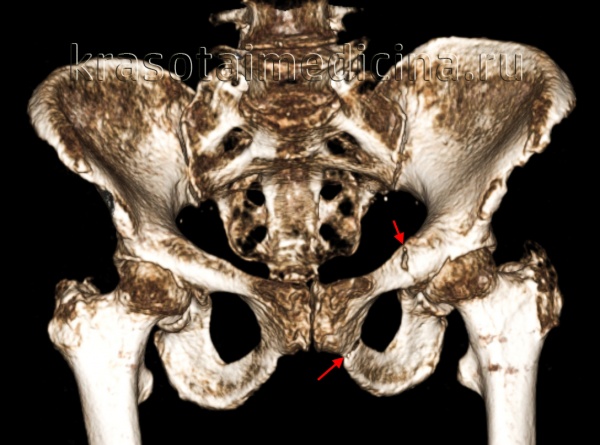

По направлению повреждающей силы выделяют переломы костей таза вследствие переднезаднего сдавления (АРС), бокового сдавления (LC), вертикального (VS) и комбинированного воздействия (СМ). Согласно классификации Тайля (Tile), все переломы подразделяются на три группы — А, В и С (включающие пронумерованные подгруппы) — на основании тяжести повреждения связочного аппарата и костей.

P.S. В России повреждения таза подразделяют на: краевые переломы, переломы тазового кольца без нарушения его непрерывности, повреждения с нарушением непрерывности тазового кольца, повреждения с одновременным нарушением непрерывности переднего и заднего полуколец (типа Мальгеня) и переломы вертлужной впадины.

- Компьютерная томография.